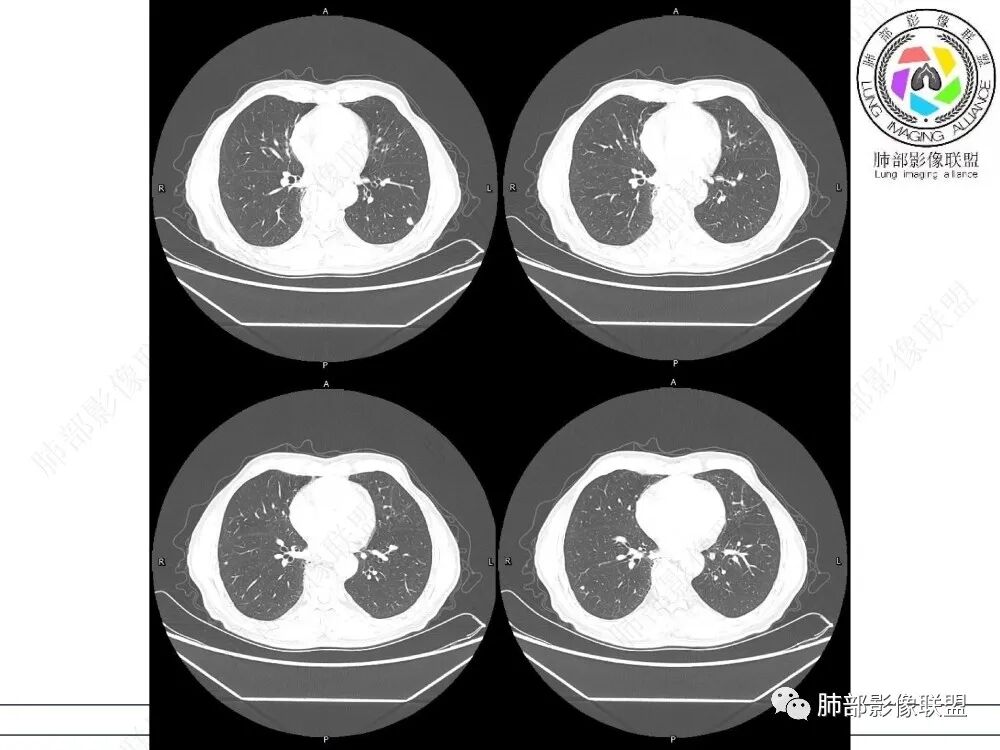

病史时间:2018年8月12日确诊左肺上叶肺腺ca射频消融,2020年1月13日左肺下叶未见结节,2021年3月14日新发双肺下叶(视频图)见4枚实性小结节,边清,目测低强化,胸膜下的结节(3个)与胸膜粘连的特点,无收缩力,前后1年余倍增明显结节,多发,支持炎性肉芽肿结节,隐球菌荚膜抗原检查,其次与转移鉴别,非随机,位置仅双肺下叶,可能性小,建议左肺下叶后基底结节定位穿刺活检!

1、临床特点:中老年男性,间断左侧胸痛2年余,复发1月余,既往左肺上叶占位穿刺确认肺腺癌,未行手术治疗,给予两次射频消融术,术后定期复查,1月前患者出现左下胸部阵发性刺痛,无畏寒、发热、咳嗽等其他临床症状,门诊胸部CT提示:左肺下叶新发结节。

2、影像特点:左肺上叶尖后段病灶结合病史考虑消融术后改变,双肺下叶胸膜下可见多发大小不等的实性结节,周围似乎有晕,边缘平直为主,未见深分叶,部分可见邻近胸膜牵拉,张力不高,增强后呈轻中度强化。

3、总结:中老年男性,间断胸痛就诊,余无明显其他临床体征。既往肺癌病史,定期复查,一年左右双肺新发多发结节,常规需要鉴别炎性肉芽肿和肺癌转移。病灶以胸膜下为主,边界清楚,尽管转移是可以的,但混合磨玻璃时期腺癌相对惰性,短期内难以出现如此转移灶。况邻近胸膜牵拉,这在转移中也相对要少见。病灶多发,但没有新旧不等,没有树芽,病灶及时间线不支持继发性肺结核。病灶散在,胸膜下为主,周围可见少许晕征,部分病灶边缘比较平直,影像上较为符合隐球菌等肉芽肿性炎。